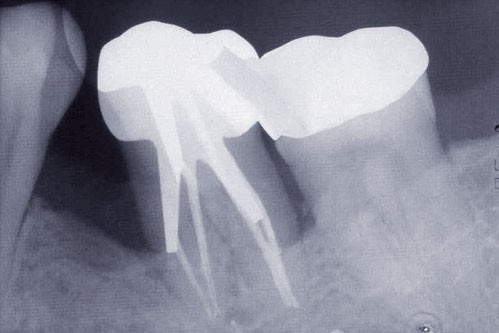

Les examens cliniques et radiographiques montrent une parodontite chronique généralisée (fig. 1a à m).

Nous décidons d’entreprendre une thérapeutique initiale parodontale classique dans tous les secteurs, y compris l’extraction de 24, un bridge de 45 à 48 avec 46 en pontique, un bridge complet de contention de 17 à 27 sur 11 piliers dentaires et une greffe épithélio-conjonctive sur 31. Cette dernière ne sera jamais réalisée. Le bridge maxillaire permettra de réduire le surplomb antérieur et d’améliorer le sourire de la patiente, ce qui constitue l’une de ses demandes.